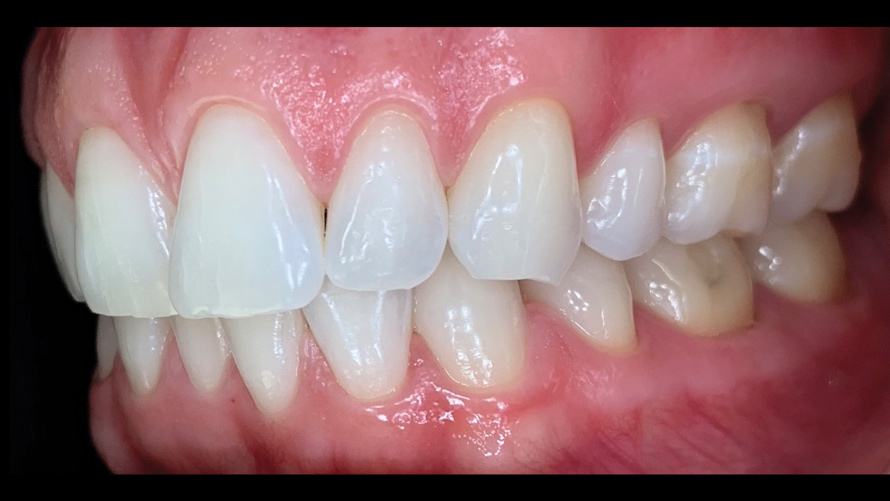

One of the main advantages that smartphone cameras have over DSLR cameras is that nearly everyone is already very familiar with the technology; therefore, the incorporation of these devices into everyday practice does not require learning a new and unfamiliar skill set. The task of producing a series of high-quality clinical photographs for routine examinations (Figure 8), esthetic treatment planning (Figure 9 through Figure 11), or specialty care (Figure 12 and Figure 13) can be delegated with confidence to any staff member during the patient's initial office visit and will generally require less than 5 minutes of time to complete. When a DSLR camera is used, evaluation of the intraoral images either takes place on the small viewfinder built into the camera or necessitates the physical removal of the memory card from the camera to downloaded the images onto a computer for review. An added bonus of smartphone dental photography is that the phone's screen now replaces the much smaller viewfinder of a DSLR camera and provides the clinician with the ability to view and zoom into the patient images on a 5- to 6-inch, high-definition display.

(8.) Routine case photograph taken with a smartphone and an EALS device.

Figure 8

(9.) Preoperative esthetic case documentation using a smartphone and an EALS device.

Figure 9

(10.) Preoperative esthetic case documentation using a smartphone and an EALS device.

Figure 10

(11.) Preoperative esthetic case documentation using a smartphone and an EALS device.

Figure 11